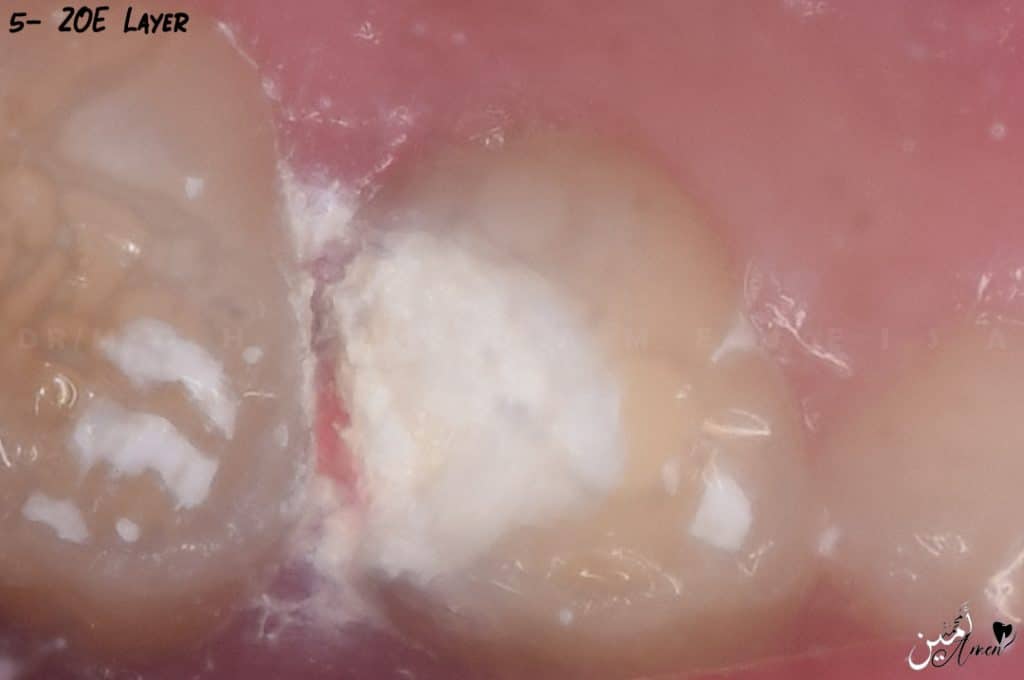

- The blood stopped, fixation layer achieved, so, you start to apply the ZOE by making a thick mix, that you can handling it like temporary filing

- You put it layer by layer, and you take a piece of cotton soaked in water and squeeze it well and hold it with a tweezer, and press comfortably on the ZOE like doing condensation, then you put the next layer on and do the same thing for another time, keep the last 4 mm for final restoration.

- If you will make SS crown, you can fill the cavity with ZOE and place the SS crown as final restoration.

- Or put a layer of the ZOE then layer of GI then SS crown

Here I put ZOE and a glass ionomer on it to make an SS crown.